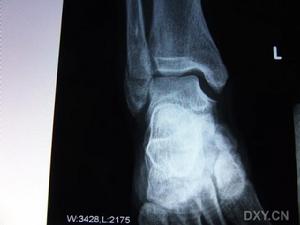

距骨骨折--石膏托外固定2、復位固定後要注意觀察足趾皮膚溫度和顏色,足背動脈搏動、毛細血管充盈時間,被動活動足趾時的反應。

4、整復後石膏托外固定病人,應注意觀察石膏托鬆緊度。

5、復位固定後定期x線檢查,觀察骨折癒合情況,距骨體有無缺血徵象。